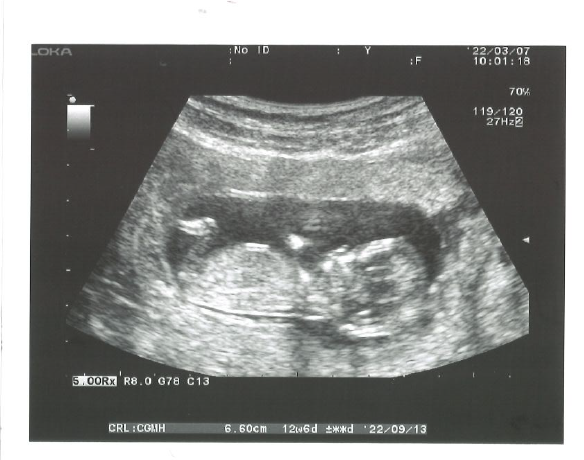

TO黃建榮醫生&團隊 非常感謝黃醫師及護士團隊在治療過程中給予耐心、關心及鼓勵,讓我能順利懷孕成功! 會來黃醫師這邊主要是經過朋友成功經驗的分享及介紹;也是因為結婚快兩年一直沒有消息,加上經過檢查醫院評估為輸卵管阻塞,考量我的年紀及可以休假的時間性,我直接選擇第三階段的療程(試管嬰兒),想到未來如果還有想生第二胎等打算,取出的卵即為當下的年齡,也可減少嬰兒健康的不確定性。 在治療過程 ...

這位好朋友很年輕今年32歲,但去年底在外院檢測卵巢功能AMH只有0.62,跟同齡人相比是低很多的,屬於卵巢早衰的現象,這種狀況其實也不是什麼原因造成,大多都是個人的體質。因此他們夫妻來到我們診所經過詳細的看診諮詢後,事不宜遲決定直接開始試管嬰兒療程。   一連串的打針用藥、回診追蹤,共取得4顆卵子培養成3顆等級不錯的胚胎,以她的取卵率及受精率都有達到60~70%,很不 ...

這位好朋友今年27歲,卵巢功能及先生精子狀況皆稍虛弱,在嘗試過兩次吃排卵藥自然同房未果後,他們決定積極的進入試管療程。   雖然她的AMH1.2偏低,但很高興的總共取到10顆卵,在第一次植入一顆新鮮胚胎沒有成功,稍作休息後再度嘗試植入一次放了兩顆胚胎,這次她順利的懷孕成功。   照片中精美的畢業糖是他們夫妻特別去訂製的,藍色的男寶寶及粉色的女寶寶希望大家 ...

這位好朋友43歲AMH0.82,至109年開始試管療程,她總共經歷8次的取卵,頭一兩次都有懷孕,但都是淺著床或是在第八週時寶寶沒有心跳,因此我建議他們之後的試管療程加上PGS。   接下來的療程PGS大多是異常或是鑲嵌型的胚胎,甚至有一次胚胎沒有長到囊胚無法切片,但皇天不負有心人,終於他們得到一顆PGS檢測正常的胚胎。   再植入胚胎之前為了謹慎起見,做 ...

這位好朋友今年33歲,夫妻雙方檢查沒有大問題,但在自然同房努力兩年都沒有好消息,所以在108年來到我們診所。 試過3~4次的排卵藥自然同房以及一次的人工授精很不幸的沒有成功,在去年10月也剛好有政府的試管嬰兒的補助,他們決定開始試管療程。 太太的卵巢功能不錯,AMH4.05總共取到16顆卵子,因為擔心取卵後會有卵巢過度刺激的可能,我們採取兩段式試管嬰兒,先將胚胎冰凍起來下個週期 ...